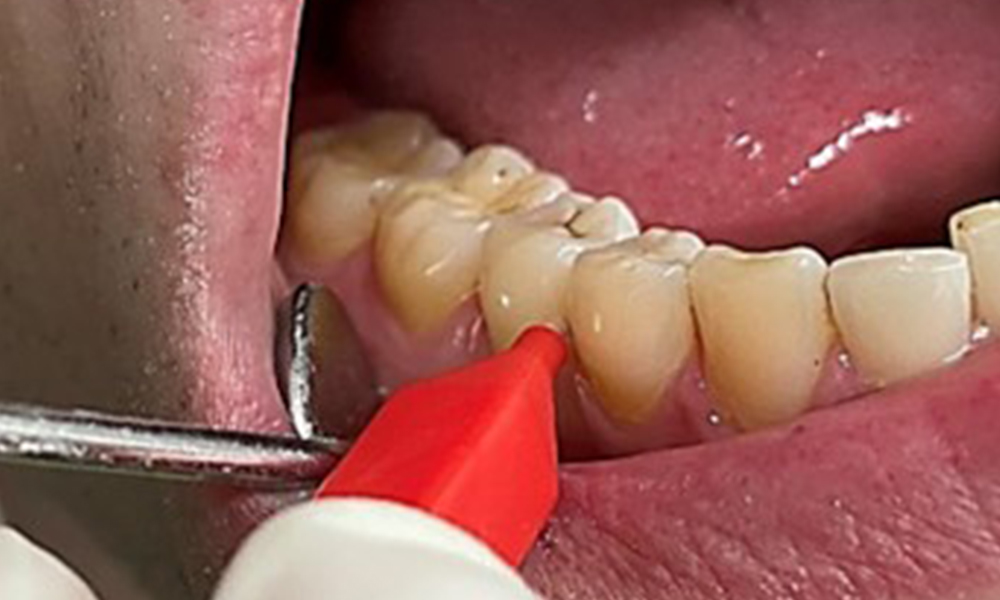

It is also necessary to check that the interdental brushes – used by this patient on a daily basis – are the correct size and encourage consistent use (Fig. 9). Good intraoral hygiene minimizes the risk of periodontitis from smoking.

Use of the interdental brushes in the area near 44/45

Fig. 9: Use of the interdental brushes in the area near 44/45, © Dr R. Krapf